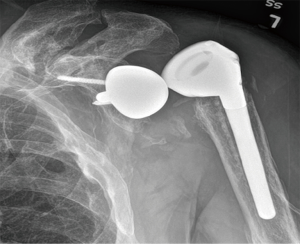

Instability is the most common postoperative complication of RSA (Figure 1), with an overall prevalence of 4.7%, and reoperation is required for the majority of cases (87.5%) (3). The prevalence of instability doubles in revisions (9.4%) compared to primary RSA (4.1%) (2). The largest case series on instability after RSA demonstrated a rate of 14.7% (6), while earlier studies reported rates up to 50% (7,12-19).

Prosthetic malalignment (Figure 2) can cause dislocation of RSA if excessive anterior version of the glenosphere and/or excessive retroversion of the humeral component, resulting in abutment of the humerosocket against the glenoid neck during internal rotation (3,6,12,15,25,34). However, it is still unclear how much misalignment of the component can be considered a risk to RSA stability.